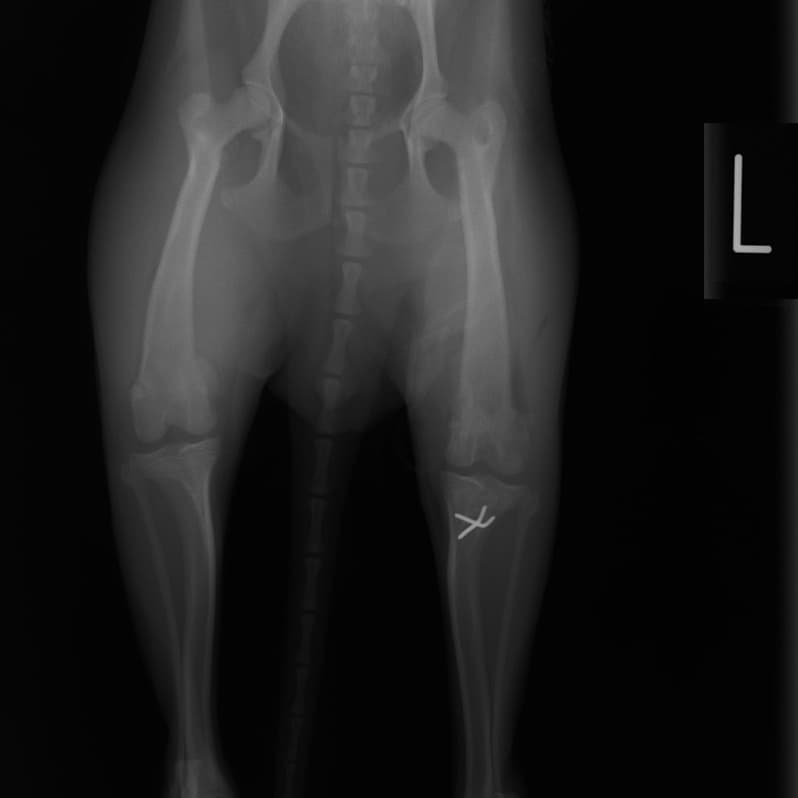

■ 症例20 ポメラニアン 8ヶ月 1.8kg

左右膝蓋骨脱臼 グレードⅢ

2ヶ月前から間欠的跛行が認められ、両膝の膝蓋骨脱臼整復術を行った。

手技は縫工筋及び内側広筋の解放、脛骨粗面の外側転位、滑車ブロック形造溝術、内外側関節包の縫縮を選択し実施した。

右側の膝蓋骨脱臼は上記手技で整復されたものの、左側はそれのみでは膝蓋骨が浮く様子が認められた。その為、PDS縫合糸にて膝蓋靱帯を1糸のみ縫合し、靱帯の縫縮を行った。

膝蓋骨脱臼は膝関節における膝蓋骨の内外側の脱臼と定義されるが、時として単純な内外の脱臼ではなく、膝蓋骨が大きく前方に浮き上がるように脱臼する場合がある。特にトイプードルやポメラニアンといった犬種に多く認められる。

内側脱臼に加えて前方への浮き上がりを矯正する為に、従来より脛骨粗面転移により膝蓋靭帯を外方と下方に引っ張り、固定する方法を選択する。膝蓋骨の前方への浮き上がりが軽度の場合は、従来法ではなく関節包の縫縮で対応していた。しかし、一部の症例で膝蓋骨の動きが悪くなり伸展機構が円滑に機能せずロボット様歩行になるケースがあった。

その為、膝蓋靭帯自体を縫縮する方法を採用した。この方法により、膝関節の伸展機構を妨げず膝蓋骨の軽度の浮きを矯正することが可能となった。

本症例の経過は良好である